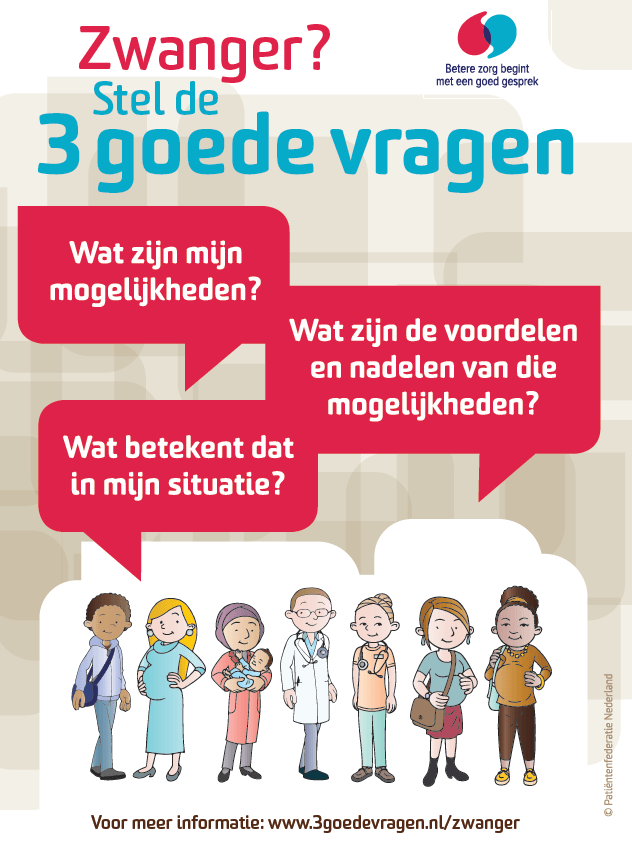

Webinar: Aan de slag met ‘3 goede vragen’

Op dinsdag 27 oktober a.s. vanaf 20.00 uur organiseert het CPZ een webinar over de methode ‘3 goede vragen’. De methode ‘3 goede vragen’ stimuleert het gesprek tussen zorgverlener en...